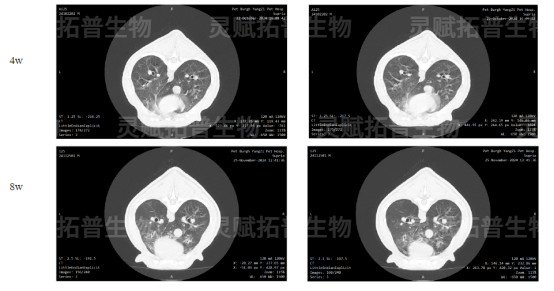

Day7/14/28/56:通过 DR-X 光、CT 扫描动态捕捉肺部影像变化(4 周斑片状阴影→8 周密度增高,纤维化进展明确);

造模4周、8周肺部CT影像图